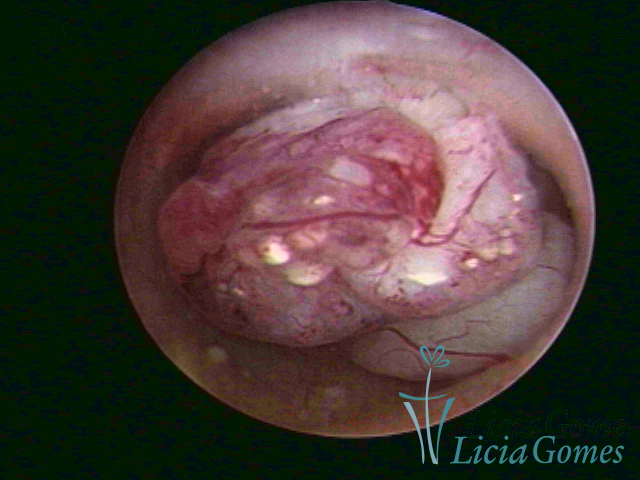

Este pode apresentar uma gama variável de aspectos macroscópicos, com aspecto pseudopolipoide; lembrando tecido cerebroide ou com reação deciduoide;a vascularização superficial é mais evidente e com vasos em formatos de saca-rolha ou espirais visualizando também a vascularização com atípias, com aumento do calibre dos vasos superficiais, pode ser encontrado também tecido em necrose, poderá haver um pequenos dendritos (papilomatoso).